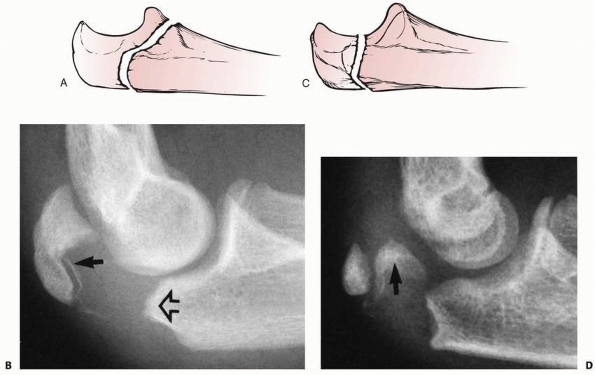

![]() |

FIGURE 11-4 A,B. AP and lateral radiographs demonstrating a radial neck fracture in a patient with a nonossified proximal radial epiphysis. C. Arthrogram prior to reduction demonstrating location/displacement of nonossified proximal radial epiphysis. D-F.

Arthrogram/radiographs after reduction with intramedullary technique. (From Javed A, Guichet J.M. Arthrography for reduction of a fracture of the radial neck in a child with a nonossified radial epiphysis. J Bone Joint Surg Br 2001;83-B:542-543, with permission.) |